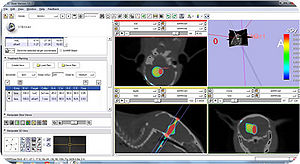

A snapshot of the module SmartModelClip in 3D Slicer. On the left is the operator command view that users can create and manipulate clipping path and thickness plane(i.e., they can create, hide and delete plane widgets). Users can also reverse the directions of the axes of the both clipping path and thickness plane widget. On the right is the scene that users can interact with the clipping path. They can specify the fiducial points that position the clipping path and modify the boundary of the clipping path by dragging the handles to obtain the desirable clipping path. |